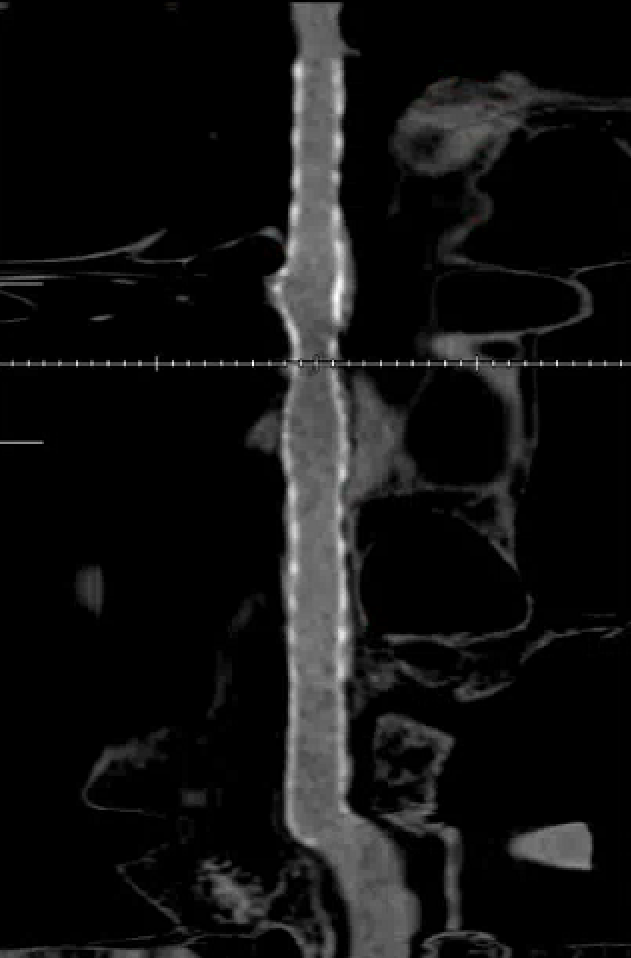

脑血管造影提示右侧颈内动脉颅内段多发动脉瘤(反主动脉弓)

脑血管造影提示右侧颈内动脉颅内段多发动脉瘤

4mm×30mm Streamline

术后4月余随访:多发动脉瘤均未见显影,远端残余轻度狭窄

术前术后对比